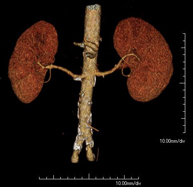

- Angio-TC aorta abdominal  Prueba diagnóstica no invasiva que consiste en el estudio de la arteria aorta abdominal obteniendo imágenes de alta definición anatómica mediante el empleo de un equipo de TC (Tomografía Computarizada) y de contraste yodado. La calidad de las imágenes permite realizar reconstrucciones en 2D y 3D gracias a estaciones de trabajo especializadas en el estudio arterial. Está indicado en aquellos pacientes con enfermedad vascular (aterosclerosis), en aneurismas de aorta, en pacientes con dolor abdominal de posible origen vascular, en estudios pre-quirúrgicos de lesiones adyacentes a la aorta abdominal como "mapa" vascular, etc. La información obtenida de forma no invasiva es indispensable para los pacientes que requieren tratamiento percutáneo o quirúrgico. En aquellos pacientes que solo requieren un seguimiento de las lesiones vasculares, esta técnica es la técnica no invasiva de elección junto con la angio-RM. Prueba diagnóstica no invasiva que consiste en el estudio de la arteria aorta abdominal obteniendo imágenes de alta definición anatómica mediante el empleo de un equipo de TC (Tomografía Computarizada) y de contraste yodado. La calidad de las imágenes permite realizar reconstrucciones en 2D y 3D gracias a estaciones de trabajo especializadas en el estudio arterial. Está indicado en aquellos pacientes con enfermedad vascular (aterosclerosis), en aneurismas de aorta, en pacientes con dolor abdominal de posible origen vascular, en estudios pre-quirúrgicos de lesiones adyacentes a la aorta abdominal como "mapa" vascular, etc. La información obtenida de forma no invasiva es indispensable para los pacientes que requieren tratamiento percutáneo o quirúrgico. En aquellos pacientes que solo requieren un seguimiento de las lesiones vasculares, esta técnica es la técnica no invasiva de elección junto con la angio-RM.

- Angio-TC arterias renales  Prueba diagnóstica no invasiva que consiste en el estudio de las arterias renales obteniendo imágenes de alta definición anatómica mediante el empleo de un equipo de TC (Tomografía Computarizada) y de contraste yodado. La calidad de las imágenes permite realizar reconstrucciones en 2D y 3D gracias a estaciones de trabajo especializadas en el estudio arterial. Esta prueba está indicada, por ejemplo, en aquellos pacientes que sufren de HTA refractaria al tratamiento, en pacientes con lesiones renales para tener un mapa "vascular" pre-quirúrgico, etc. Prueba diagnóstica no invasiva que consiste en el estudio de las arterias renales obteniendo imágenes de alta definición anatómica mediante el empleo de un equipo de TC (Tomografía Computarizada) y de contraste yodado. La calidad de las imágenes permite realizar reconstrucciones en 2D y 3D gracias a estaciones de trabajo especializadas en el estudio arterial. Esta prueba está indicada, por ejemplo, en aquellos pacientes que sufren de HTA refractaria al tratamiento, en pacientes con lesiones renales para tener un mapa "vascular" pre-quirúrgico, etc.

- Angio-TC aorto-ilíaco Prueba diagnóstica no invasiva que consiste en el estudio de las arterias ilíacas y la aorta abdominal obteniendo imágenes de alta definición anatómica mediante el empleo de un equipo de TC (Tomografía Computarizada) y de contraste yodado. La calidad de las imágenes permite realizar reconstrucciones en 2D y 3D gracias a estaciones de trabajo especializadas en el estudio arterial. Esta prueba está especialmente indicada como estudio pre-quirúrgico (mapa vascular) antes de intervenciones percutáneas o quirúrgicas de aorta abdominal, como el estudio complementario en pacientes con isquemia de miembros inferiores, etc. Prueba diagnóstica no invasiva que consiste en el estudio de las arterias ilíacas y la aorta abdominal obteniendo imágenes de alta definición anatómica mediante el empleo de un equipo de TC (Tomografía Computarizada) y de contraste yodado. La calidad de las imágenes permite realizar reconstrucciones en 2D y 3D gracias a estaciones de trabajo especializadas en el estudio arterial. Esta prueba está especialmente indicada como estudio pre-quirúrgico (mapa vascular) antes de intervenciones percutáneas o quirúrgicas de aorta abdominal, como el estudio complementario en pacientes con isquemia de miembros inferiores, etc.